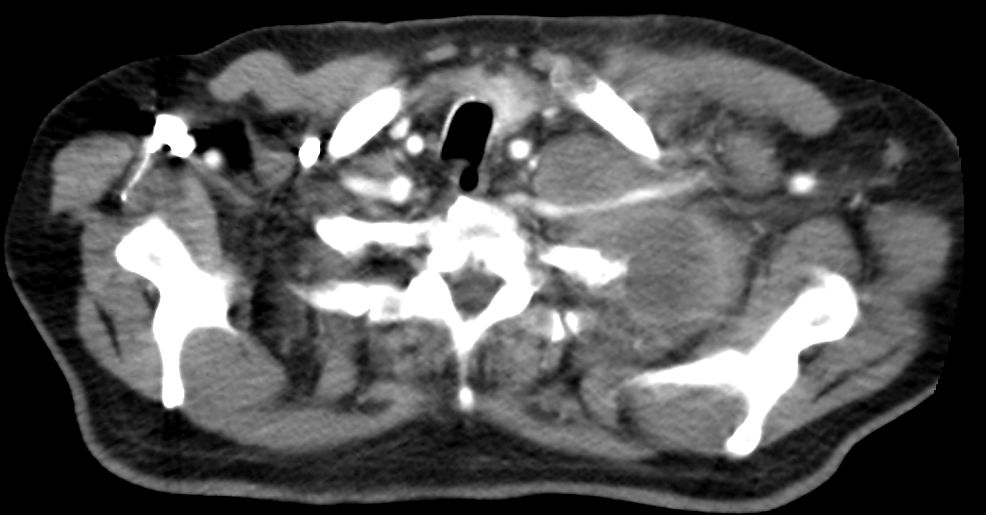

| Supraclavikuläre Lymphknotenmetastase | Lymphknotenmetastase unter der medialen Clavikula

links. ![]() |